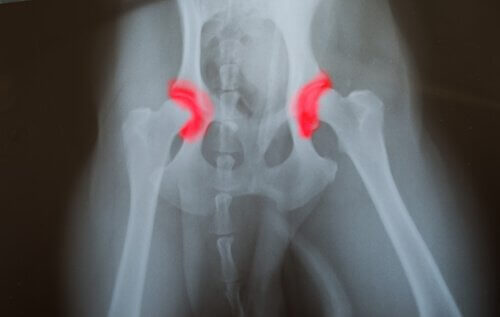

Armbågs- eller höftledsdysplasi är en ärftlig sjukdom som går från generation till generation. Den orsakas av att de ben som utgör en led – vare sig det rör sig om höften eller armbågen – inte är rätt placerad.

Detta får dem att gnuggas mot varandra och orsaka felaktiga rörelser. Detta orsakar i sin tur en nedbrytning vilket kan leda till att lederna inte fungerar som de ska.